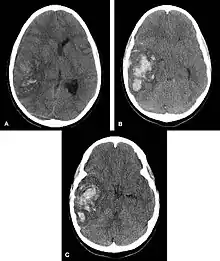

![]() | |

| Multiple intraparenchymal hemorrhage | |

Hemorrhagic neoplasms are more complex, heterogeneous bleeds often with associated edema. These hemorrhages are related to tumor necrosis, vascular invasion and neovascularity. Glioblastomas are the most common primary malignancies to hemorrhage while thyroid, renal cell carcinoma, melanoma, and lung cancer are the most common causes of hemorrhage from metastatic disease.

Nontraumatic intraparenchymal hemorrhage most commonly results from hypertensive damage to blood vessel walls e.g.: - hypertension - eclampsia - drug abuse, but it also may be due to autoregulatory dysfunction with excessive cerebral blood flow e.g.: - reperfusion injury - hemorrhagic transformation - cold exposure - rupture of an aneurysm or arteriovenous malformation (AVM) - arteriopathy (e.g. cerebral amyloid angiopathy, moyamoya) - altered hemostasis (e.g. thrombolysis, anticoagulation, bleeding diathesis) - hemorrhagic necrosis (e.g. tumor, infection) - venous outflow obstruction (e.g. cerebral venous sinus thrombosis). Nonpenetrating and penetrating cranial trauma can also be common causes of intracerebral hemorrhage.